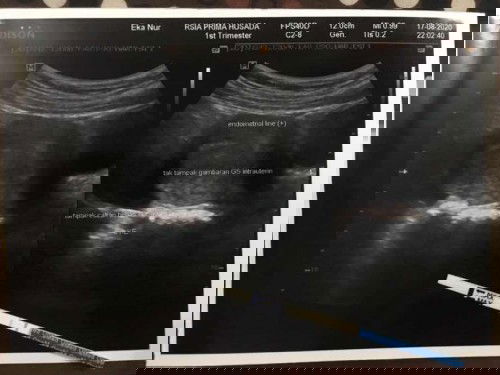

Mungkin ada yang pernah mengalami tanda-tanda seperti saya, jika terhitung sejak awal terakhir mens tgl 14juli2020 sekarang usia kehamilanku 4 minggu 3hr, mual belum cuman lebih terasa lelah Dan kadang perut sedikit kram Hari ini 17/8/20 aku cek usg dan si lingkaran janin belum terlihat tetapi ada penebalan dinding rahim, dokter bilang 2 minggu lg bisa usg lagi, jadi apakah ada yang mengalami hal sama seperti saya?